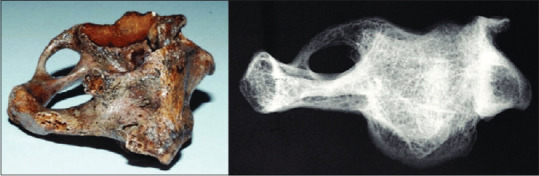

Background and objectives: Ponticulus posticus (PP), also known as arcuate foramen or Kimmerle's anomaly, is an atlas (C1) bone anomaly in the form of a bone bridge. This study aims to determine the prevalence of PP in two hospitals in Surabaya, Indonesia, and to determine the risk factors for PP and its impact on the thickness of the C1 lamina.

Results: The study found a prevalence of PP of 15.7%. The mean thickness of the posterior arch lamina with PP was 3.3 ± 0.95 mm on the right side and 3.4 ± 1.0 mm on the left side. Although these figures are not statistically significant, both were thinner than the lamina without PP. The study also found that the prevalence of PP increases with age, with a significant value of P < 0.001.